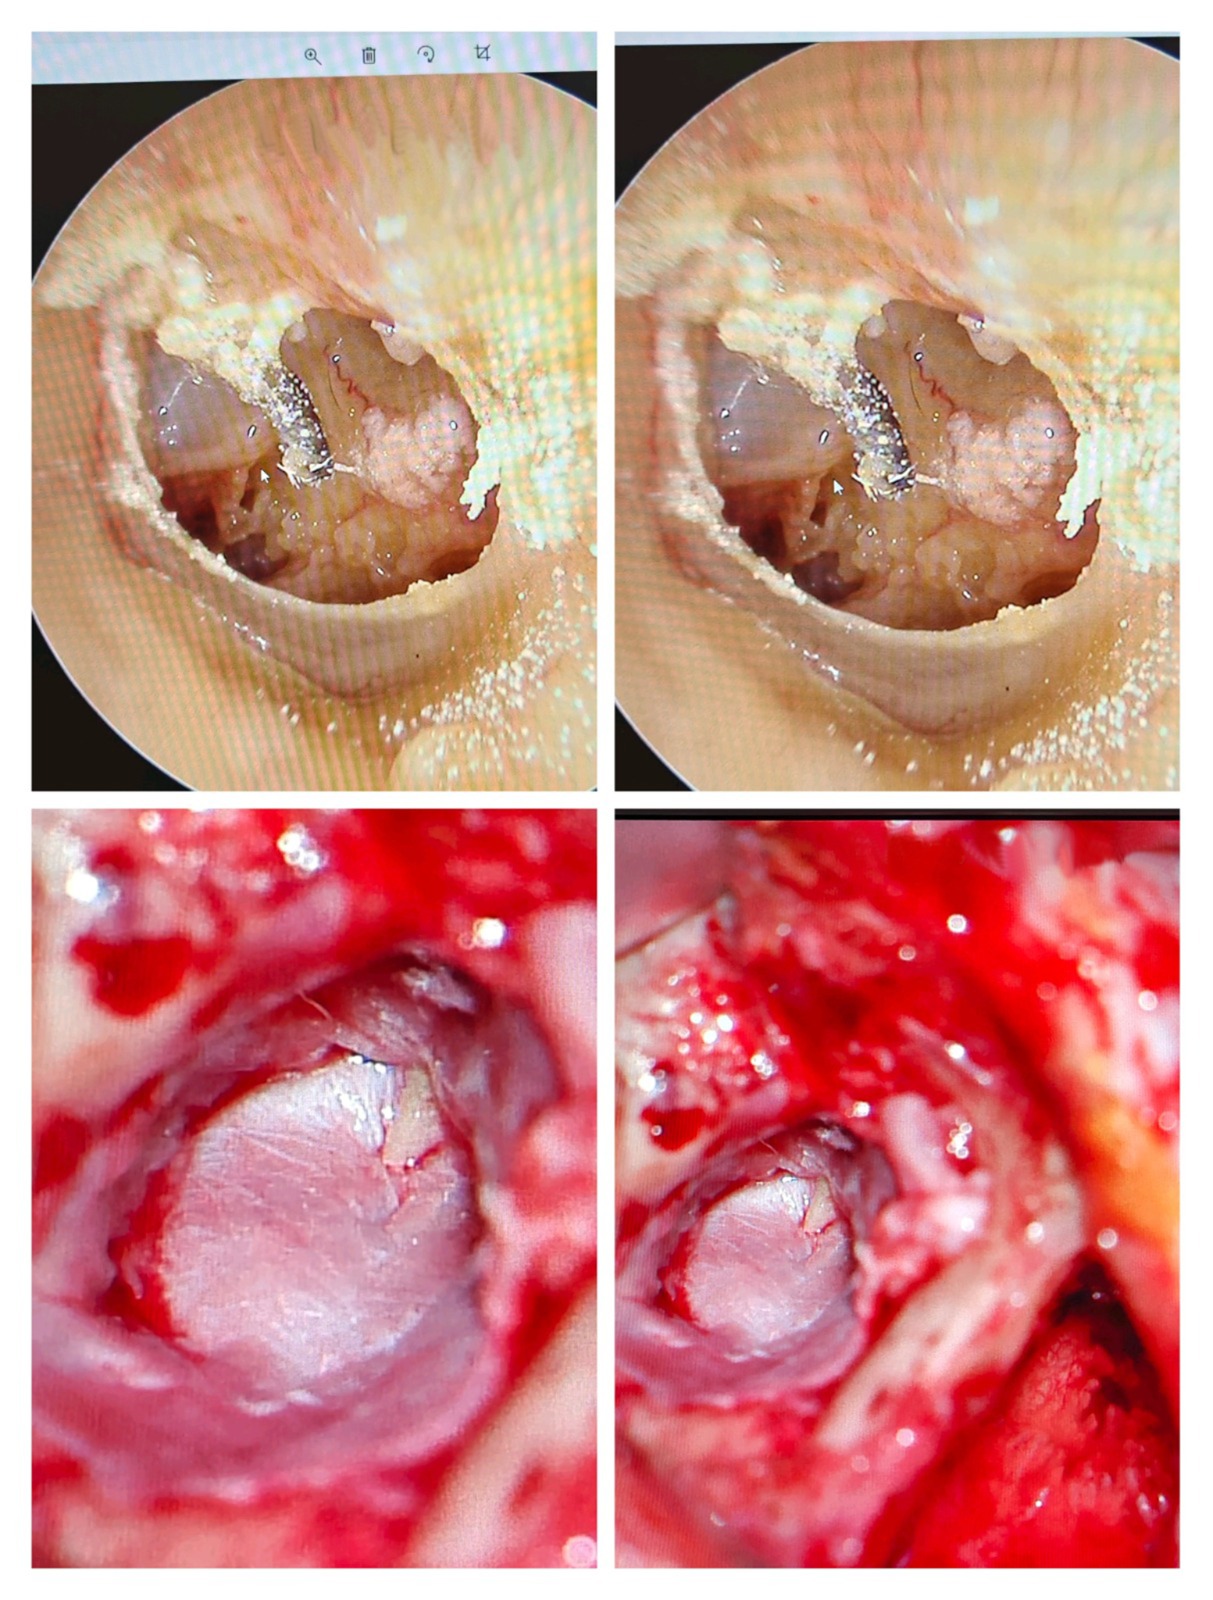

1. Tympanoplasty (Eardrum Repair Surgery)

Tympanoplasty repairs a perforated or damaged eardrum using advanced microscopic techniques.

2. Stapedotomy (Otosclerosis Hearing Surgery)

Stapedotomy is performed when the stapes bone becomes fixed due to otosclerosis, causing hearing loss.

Dr. Muddazir replaces the fixed stapes bone with a prosthetic, restoring natural sound conduction.

3. Ossiculoplasty (Middle Ear Bone Reconstruction)

Ossiculoplasty reconstructs or replaces damaged ossicles (hearing bones: malleus, incus, stapes).

- High-definition microscopes

- Infection control standards

- Nerve-monitoring systems